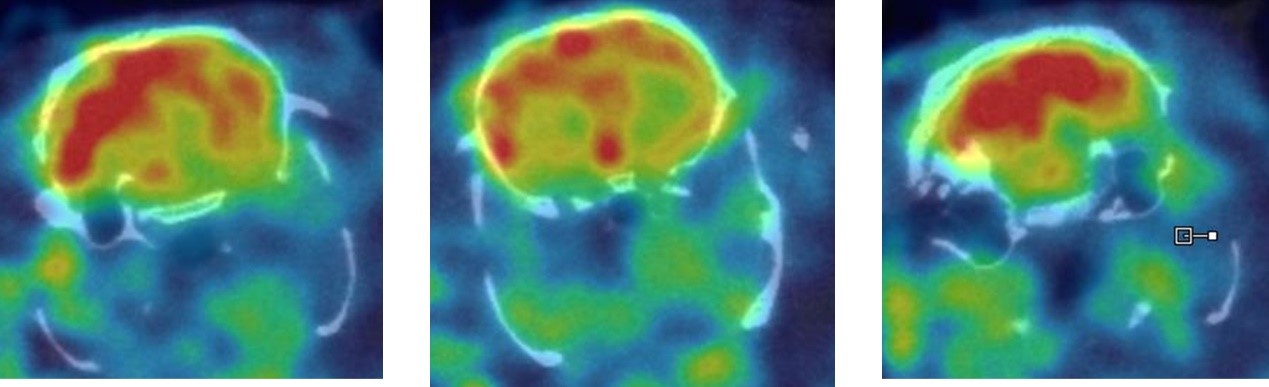

1、SPECT imaging of nervous system

Brain SPECT imaging in rats: 99mTc-HMPAO: cerebral blood perfusion imaging agent for the diagnosis of cerebrovascular diseases, brain trauma, epilepsy, dementia, and brain death; It is used to study the brain function of mental illness and normal brain physiological function. 99mTc-HMPAO, which enters the brain tissue, changes its configuration and becomes a water-soluble compound, which cannot pass the blood-brain barrier again and remain in the cell, so it can remain in the brain for a long time. 120 MBq, 30 min uptake, 30 min SPECT.